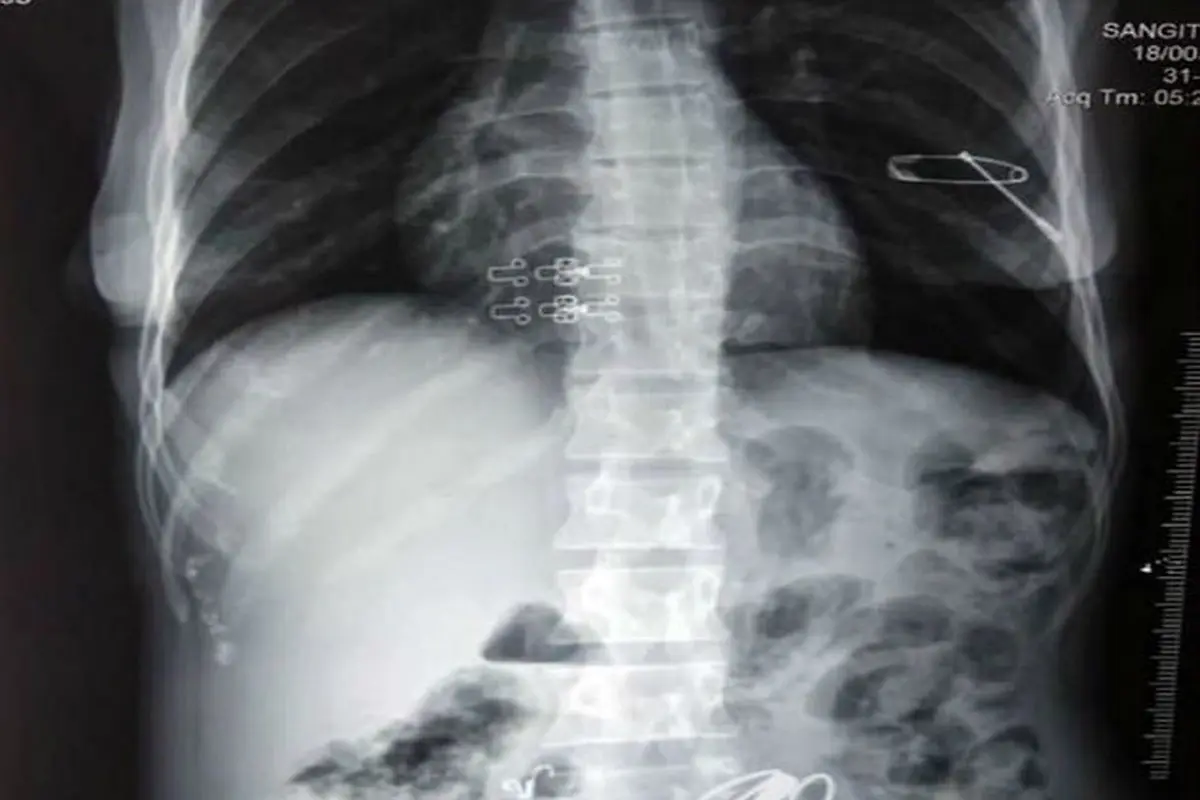

این اشیا شامل پیچ و مهرهها و جواهرات و سنجاق و طناب بود که در طی 3 ساعت جراحی از بدن این پیرزن خارج شد. تصاویر رادیوگرافی نشان میدهند که برخی از این اجسام نوک تیز به ریه این فرد نزدیک شده بودند.

یک سوزن نیز دیواره معده این زن هندی را سوراخ کرده بود که پزشکان را مجبور به جراحی اورژانسی کرد.